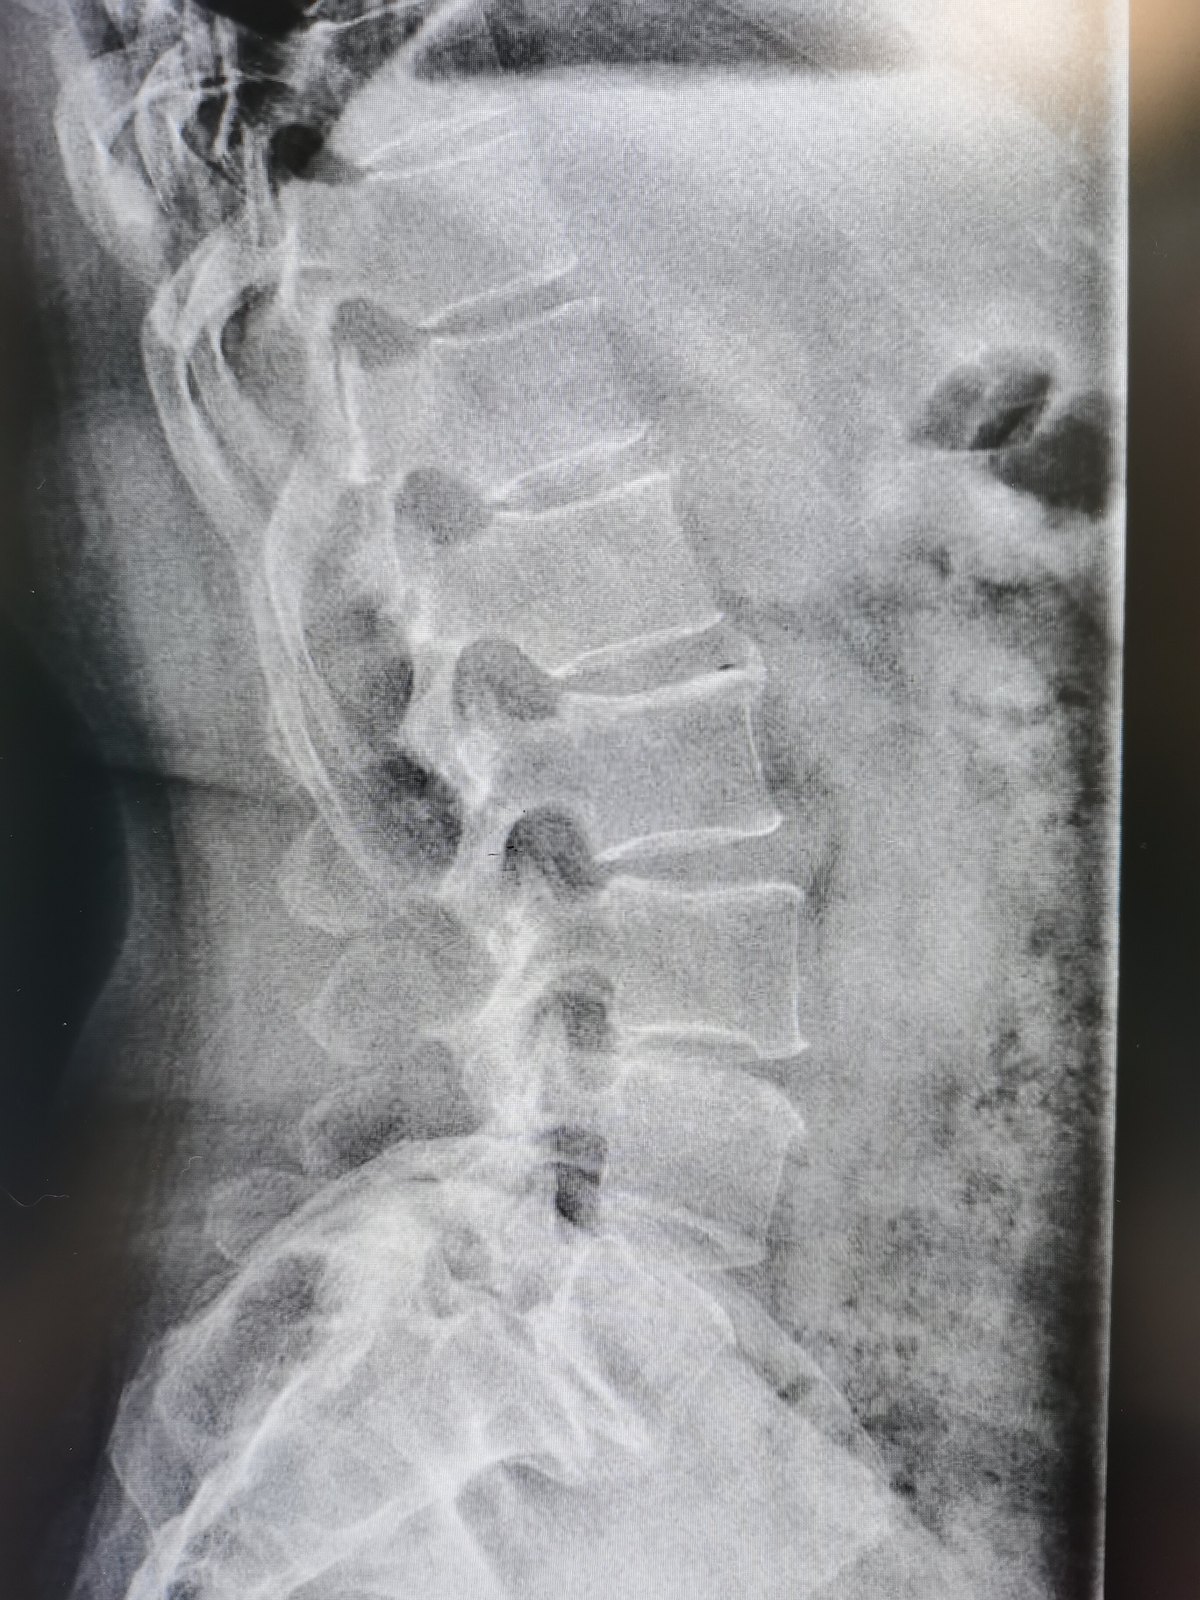

腰椎滑脱术后可能出现的后遗症包括以下几类1 疼痛术后可能出现腰部或下肢的持续性疼痛,原因包括手术部位炎症反应神经根受压或周围肌肉损伤疼痛程度因人而异,部分患者需通过药物或物理治疗缓解2 神经损伤手术操作可能损伤神经根,导致下肢麻木无力放射性疼痛,甚至影响膀胱或肠道功能如大小。

腰椎滑脱术后可能出现的后遗症主要包括以下几类1 腰痛未完全缓解部分患者术后仍存在持续性腰痛,可能与手术部位瘢痕组织形成邻近关节突关节退变或术后腰椎生物力学改变有关这种疼痛可能长期存在,但通常较术前减轻,需通过康复训练或物理治疗改善2 脑脊液漏手术中若硬脊膜被意外损伤,可能导致脑。

腰椎滑脱术后可能出现的后遗症主要包括以下几方面短期残留症状术后短期内一般持续36个月,部分患者可能出现症状残留,如疼痛未完全消退麻木感减轻缓慢或跛行症状改善不明显这可能与神经适应新环境的过程有关,即神经在术后从失代偿状态恢复时,对新的力学环境产生“不耐受”若症状未伴随。

腰椎滑脱术后可能出现的后遗症及处理方式如下一短期残留症状术后部分患者可能因神经重新适应新环境,出现短期残留症状,表现为原有疼痛麻木跛行未缓解甚至加重,但无肌力明显下降此类症状通常与神经在失代偿状态下突然复位后的“不适应”有关,持续时间多为36个月,多数患者可自行缓解,无需。

腰椎滑脱手术可能存在的后遗症主要包括以下几类1 出血相关并发症手术过程中可能因充分减压操作导致出血,分为术中出血和术后出血术后出血若积聚于椎管内,可能形成血肿,压迫神经或脊髓,引发肢体麻木无力甚至瘫痪等严重后果2 硬膜损伤及脑脊液漏长期腰椎滑脱患者,硬膜与周围组织可能因慢性炎症形。